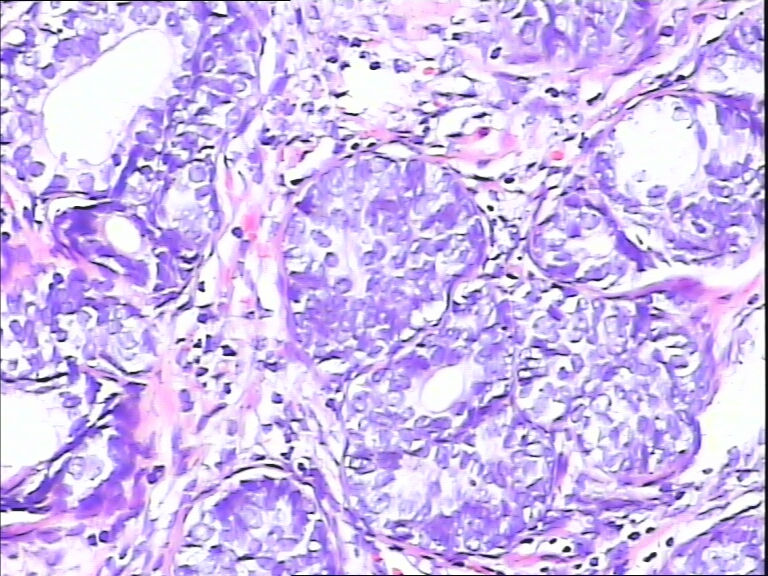

看不到核仁,PIN3。

筛状结构,可见小核仁,做一下标记:P63、34βE12,如果阴性,则是前列腺腺癌。

作P63、34βE12、P504S

良性增生。

基底细胞增生

结构复杂,核大但其染色欠佳,建意做免疫组化

感觉肌上皮细胞存在,良性增生?

考虑前列腺良性增生伴基底细胞增生,但细胞模糊,建议再切片染HE或IHC鉴别诊断。

考虑HGPIN

前列腺增生症,局部呈PIN改变,建议免疫组化进一步明确

基底细胞增生?HPIN?前列腺癌?

只有做标记了才放心。P63, 34BE12,P504S

前列腺腺样基底细胞肿瘤,可做:34βE12,CK5/6,P63,PSA,P504S标记进一步证实。

增生的都是基底细胞,可有核仁

筛状结构,可见小核仁,初步考虑PIN3,建议做免疫组化,34βE12,CK5/6,P63,PSA,P504S标记进一步证实。

片子切的不太好,有点厚,觉得恶性不能除外,不做免疫组化我是不敢发了

前列腺腺癌